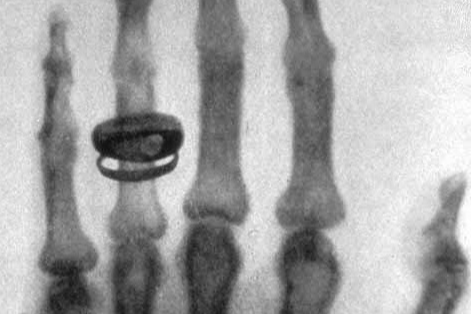

이 X-선은 보통 빛과 달리 사람의 피부나 옷을 통과할 수 있어, 뼈와 내부 장기의 모습을 처음으로 눈으로 확인할 수 있는 획기적인 방법이 되었어요. 뢴트겐은 곧 아내의 손을 촬영했고, 뼈와 반지가 선명하게 드러난 사진은 세상을 놀라게 했습니다.